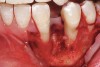

Figure 4  Vertical ridge defect in site No. 22.

Figure 4

Figure 5  Horizontal ridge defect in site No. 22.

Figure 5

The patient had no medical concerns and had a history of an implant placement in December 2002 when she was 25 years old. In February 2005, she presented with a mobile implant and an associated advanced peri-implantitis. Radiographic review at the initial examination demonstrated significant destruction of the dentoalveolar ridge around the implant as well as around the adjacent natural dentition. Emergency-based treatment involved surgical implant removal only and debridement of the infection (Figure 4 and Figure 5). Following uneventful healing, an advanced ridge defect was apparent at the edentulous site and moderate and advanced attachment loss noted at No. 22D and No. 21M, respectively (Figure 6 and Figure 7). This case demonstrates bone loss of two separate origins: lack of bone because of tooth agenesis and destruction of bone from inflammatory peri-implantitis.